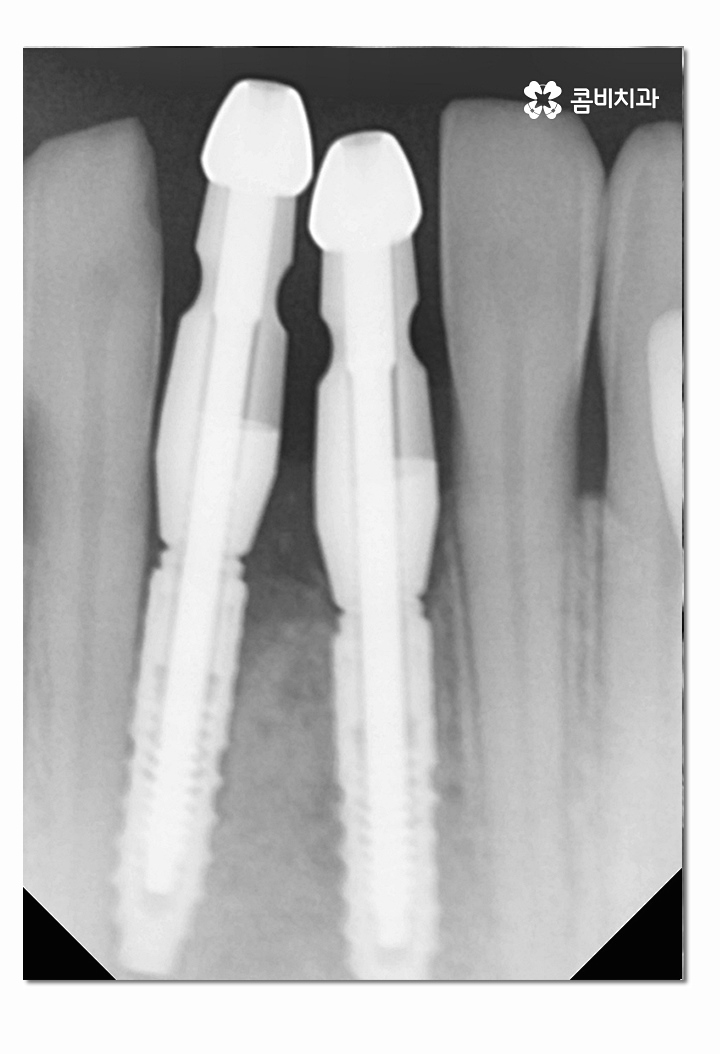

위 사진은 인공치근이 식립된 상태이고 인공치근이

잇몸뼈와 잘 유착이 되는지 확인하는 기간을

갖는 것이며 보철물을 결합하기 전에는 임시치아를 부착하고 있어요.

(좌 - 임플란트 식립 후 임시치아를 부착하고 안전하게 골 유착이 되도록 기다리는 과정, 보철물과 결합 준비 - 우)